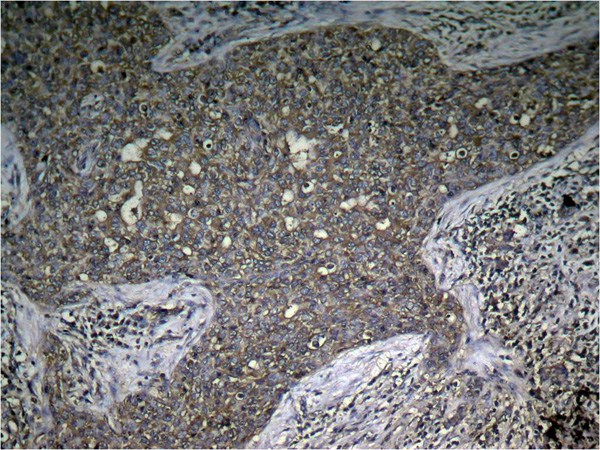

IHC (Immunohistochemistry)

(Immunohistochemical analysis ofparaffin-embedded human breast carcinomatissue using mTOR (Phospho-Ser2448) Antibody)